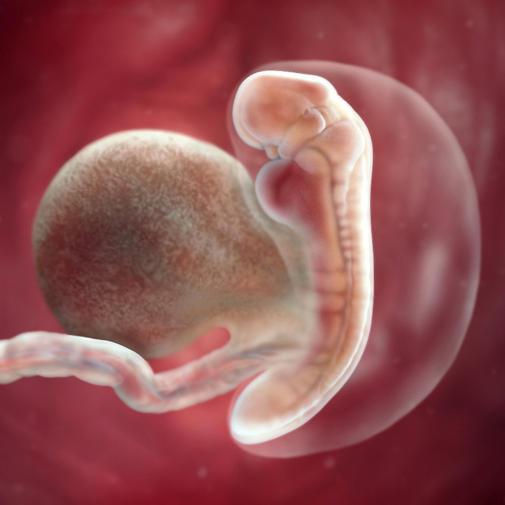

Dvouvrstevný zárodečný terčík se začíná 5. týden těhotenství prodlužovat. Mezi vnějším a vnitřním zárodečným listem vzniká střední zárodečný list – mezoderm. V 5. týdnu těhotenství (asi 17. den vývoje po oplodnění) jsou založeny všechny 3 zárodečné listy – trojvrstevný zárodek. Ze zárodečných listů vznikají později všechny tělní tkáně a orgány. Z vnitřní vrstvy (entodermu) se vyvíjí základ plic, jater, trávicího systému a slinivky břišní. Z mezodermu (střední vrstvy) se vyvíjí kostra, svaly, ledviny, cévy a srdce. Zevní vrstva (ektoderm) je základem pro vznik nervového systému, kůže, oční čočky a zubní skloviny.

Mozek a mícha vznikají nejprve přeměnou vnější části zárodku na nervovou ploténku. Z ní se vyvine základ nervové trubice. Její horní konec se zvětšuje do základu mozku, z dolní štíhlejší části vzniká základ hřbetní míchy. Po jejich stranách se začnou rýsovat základy obratlů.

Pro zajištění výživy zárodku je nezbytně nutné časné založení vlastního krevního oběhu. Jeho první základ tvoří krevní ostrůvky ve žloutkovém váčku, z nich se postupně vyvinou jednoduché cévy, které obsahují krvinky. Již před koncem 5. týdne je krevní oběh tvořen jednoduchou trubicí se základem srdce. Srdeční základ začíná tepat a krev začíná proudit již na konci 5. týdně těhotenství (3. týdny od oplození) - krevní oběh je tedy prvním systémem, který se ujímá funkce.

V této době je tedy zárodek (embryo) vzpřímený, na horním konci dominuje tlustý, dosud neuzavřený základ mozku, pod ním jsou v podobě jamky založena primitivní ústa, pod nimi je základ srdce.

Během tohoto týdne se kulatá masa buněk prodlouží a je patrná hlava a ocas. Na hlavičce se vytvořily základy pro oči a uši, vytváří se srdeční stěny tak, aby na konci týdne mohlo začít srdíčko pracovat. Začala se vyvíjet také trávicí soustava a ledviny, svalovina a kostra. Živiny čerpá ze žloutkového váčku, děložních stěn a už také z placenty.

Na konci 5. týdne měří zhruba 2 mm.Váha embrya je zhruba 1 gram.